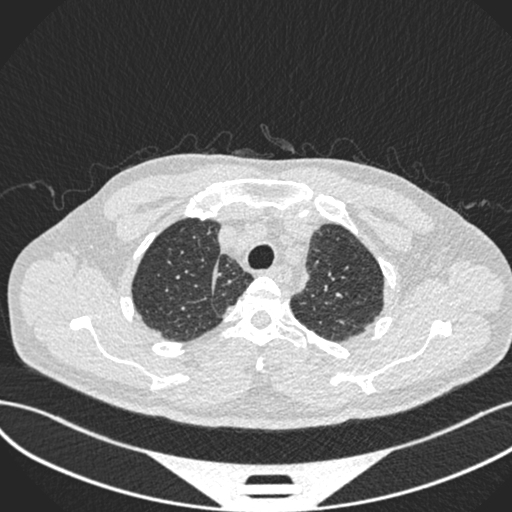

• Analyzes CT scan images using a convolutional neural network

Deep Learning A CNN-based image classifier using a modified ResNet18 trained on lung CT scans.

• ResNet18 model (224×224 RGB input)

Model generalization CT datasets vary significantly in resolution, contrast, and labeling quality. I had to refine preprocessing pipelines to ensure consistent inference.